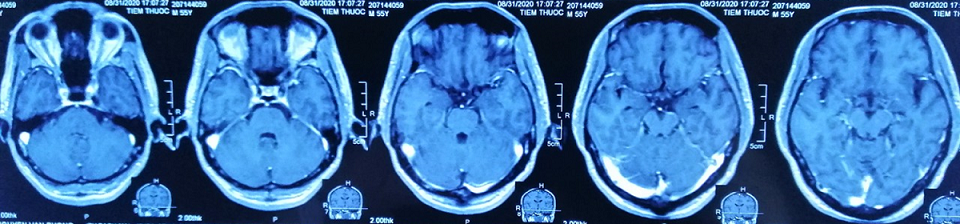

Chụp cộng hưởng từ sọ não:

Hình 3: Chụp cộng hưởng từ sọ não: Chưa phát hiện tổn thương thứ phát.